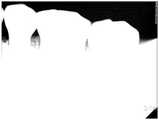

상기와 같이 반전 이미지(Irsb-30)가 생성되면, 마지막으로 원이미지(I0)에서 상기 반전 이미지(Irsb-30)를 디지털 공제 처리(I0-Irsb-30)하여 최종 치아우식 이미지(Is0-I(rsb-30))를 생성한다.(S160)When the inverted image Irsb-30 is generated as described above, the final dental caries is finally obtained byperforming a digital subtraction process I0 -Irsb-30 on the inverted image Irsb-30 from the original image I0 . and generates an image(s0 I -I(30-rsb)). (S160)

도 3f는 상기 S160과정에 의해 생성된 최종 치아우식 이미지(Is0-I(rsb-30))를 도시한 것이다.Figure 3f shows a final image of dental caries(s0 I -I(30-rsb)) produced by the process of S160.

도 3a의 원 이미지(I0)와 도 3f의 최종 치아우식 이미지(Is0-I(rsb-30))를 육안으로 비교해도 알 수 있듯이, 원 이미지 만으로는 치아우식증 정보에 대한 육안 판별이 불가능 하지만 최종 치아우식 이미지(Is0-I(rsb-30))는 원 이미지에 비해 이미지 선명도가 대폭 증가되어 육안으로 치아우식증 정보 판단이 가능하며, 이를 통해 치아우식증 진단이 가능하다.As can be seen by visually comparing the original image (I0 ) of FIG. 3A and the final dental caries image (Is0 -I(rsb-30) ) of FIG. 3F, the visual identification of dental caries information is not possible using the original image alone. The final dental caries image (Is0 -I(rsb-30) ) is significantly increased in image sharpness compared to the original image, so that the dental caries information can be determined with the naked eye.

상기 모든 이미지 변환 과정을 통해 획득된 최종 치아우식 이미지(Is0-I(rsb-30))의 진단의 장점은 도 3a의 P1, P2의 부분을 치과생리해부학적 구조에 의해 치아우식증의 증상 유무를 판단하기에 다소 주관적인 것을 상기 모든 이미지 변환 과정을 거쳐 도 3f의 P1', P2'로 이미지 개선 변환되어 구강악안면방사선과에서 구내방사선영상을 육안으로 치아우식의 소견을 객관적으로 판단하는 것이 가능하다.The advantage of the diagnosis of the final dental caries image (Is0 -I(rsb-30) ) obtained through all the above image conversion processes is that the parts of P1 and P2 of FIG. It is somewhat subjective to judge the presence of symptoms through the above image conversion process, the image is improved and converted into P1 ', P2 ' of Fig. 3f to objectively judge the findings of dental caries by visualizing intraoral radiographs with the oral and maxillofacial radiology department. It is possible.

도 3a는 원 이미지(I0), 도 3b는 상기 원 이미지(I0)의 이진이미지(Ib), 도 3c는 상기 원 이미지(I0)의 3배 이미지(3I0), 도 3d는 이진 이미지(Ib)로부터 3배이미지(3I0)를 디지털 공제 처리(Ib-3IO)를 수행하여 디지털 공제된 이미지(Isb-30), 도 3e는 디지털 공제된 이미지(Isb-30)를 이미지 반전하여 생성된 반전이미지(Irsb-30), 도 3f는 상기 반전이미지(Irsb-30)를 상기 원 이미지(I0)로부터 디지털 공제 처리(I0-Irsb-30)하여 생성된 최종 치아우식 이미지(Is0-I(rsb-30))를 도시한 것이다.Figure 3a is the original image (I0), Fig. 3b shows the original binary image (Ib), Figure 3c triple image (3I0) of the original image (I0), Fig. 3d of the image (I0) is binary image (Ib) 3 times the digital image subtraction process(3I 0) (I b -3I O) the image carried by the digital subtraction (Isb-30), Figure 3e is a digital subtraction image (Isb- from30 is an inverted image (Irsb-30 ) generated by inverting the image, and FIG. 3F illustrates a digital subtraction process (I0 -Irsb-30 ) of the inverted image (Irsb-30 ) from the original image (I0 ). the resulting final dental caries image(s0 I -I(30-rsb)) to illustrate.